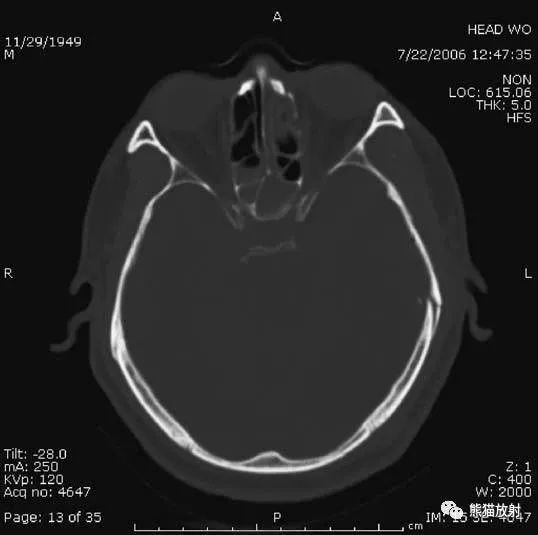

1、颅底层面眦耳线层面

颅前窝底部:眼眶、眼球、筛窦、蝶窦、前床突等。

颅中窝:前界——蝶骨;后界——颞骨岩部(岩骨);内缘——海绵窦及垂体窝;外缘——颞骨,窝内为颞叶,其内侧为海马回。

颅后窝:前缘——岩骨;后缘——枕骨;鞍背后方——脑桥前池,向两侧延伸为脑桥小脑角池。

第四脑室:位于颅后窝中线上,后面紧邻小脑蚓部,其两侧为小脑扁桃体。

延髓、脑桥:位于第四脑室前。